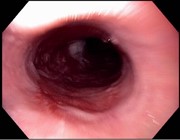

SVC obstruction and stridor relieved by nasogastric tube insertion

Emma J. Molena and others

Journal of Surgical Case Reports, Volume 2016, Issue 3, March 2016, rjw022, https://doi.org/10.1093/jscr/rjw022